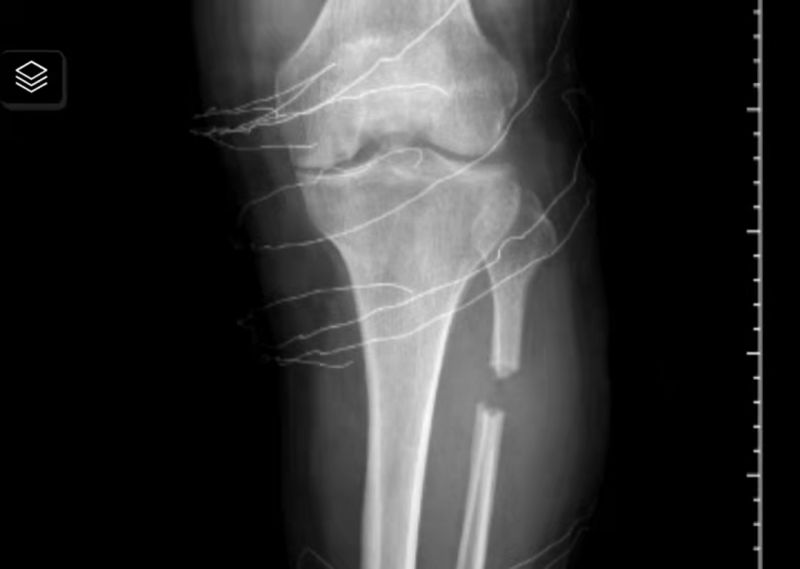

无需任何耗材植入的PFO截骨术后

与传统的膝关节周围截骨术相比,成功副主任及团队开展的系列保膝手术,不但能处理关节外的问题,也可以通过关节镜技术有效治疗关节内半月板损伤及软骨剥脱等疾病。除此之外,相对于全膝关节置换术,膝关节周围截骨术有以下6点优势:1.完整保留原装膝关节,手术完全在膝关节框架之外进行,关节的软骨、韧带完全保留,关节原有的运动模式也被完整保留;2.可最大限度精准而有效的纠正下肢力线的异常,矫正“罗圈腿”或“O”型腿;3.可恢复患者对运动功能的渴望与需求;4.OWHTO未去除任何膝关节外骨量,为患者最大程度保留了原装下肢;5.术后功能锻炼痛苦小,康复周期短;6.手术切口、出血量及创伤均明显小于全膝关节置换。